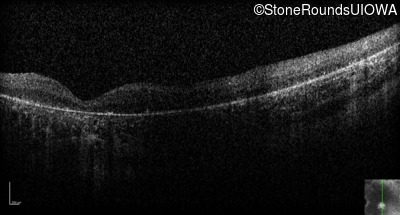

Optical Coherence Tomography - Left - Hand Motion 6" sc

Exemplar / OCT Stack